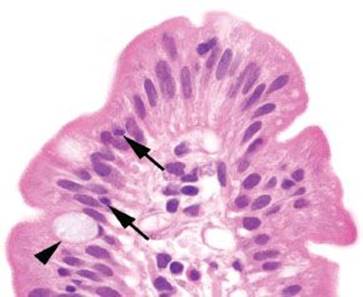

Figure 3.6 Normal small bowel, villous tip. The villous tip is lined by columnar cells with an absorptive brush border composed of microvilli. On H&E stain, this can be visualized as an eosinophilic “fuzzy” border. These absorptive columnar cells are punctuated by goblet cells (arrowhead), and small numbers of lymphocytes (arrows) may be seen traversing between them.

Figure 3.9 Normal small bowel, crypt base. Paneth cells (arrowheads) contain abundant brightly eosinophilic coarse granules that face the gland lumen. By comparison, enteroendocrine cells (arrows) have deeper red and smaller granules that face the basement membrane.